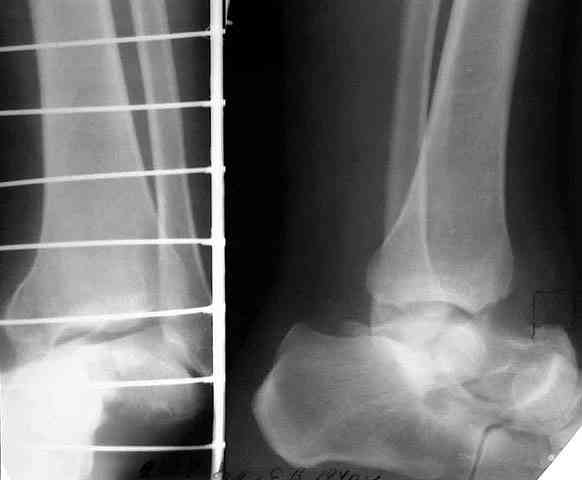

Глубокоуважаемые коллеги! Просим совета в лечении пациента с последствиями тяжелой сочетанной травмы. Пациент С., 41 года, по профессии бизнесмен, в сентябре 2005 г. пострадал в дорожно-транспортном происшествии (упал с мотоцикла). Диагноз: ЗЧМТ, ушиб головного мозга тяжелой степени. Открытый переломо-вывих левой таранной кости. Закрытые переломы лонной и седалищной костей слева. Был доставлен в НИИСП им. Н.В. Склифосовского. При ПХО раны выявлен открытый перелом левой таранной кости (III тип по Hawkins) с утратой вывихнутого тела таранной кости. Выполнена ПХО, фиксация голени и стопы стержневым аппаратом. Рана зажила без осложнений. Аппарат демонтирован через 1,5 месяца. В настоящее время больной предъявляет жалобы на боль в голеностопном суставе при нагрузке. Передвигается с опорой на костыли с дозированной нагрузкой на левую стопу.Голень и стопа фиксированы циркулярной пластиковой повязкой. Сохраняются остаточные явления ЧМТ (в виде сниженной критики к своему состоянию и определенной недисциплинированности в выполнении врачебных рекомендаций) Рентгенограммы – рис. 1, 2 (просим извинения за низкое качество рентгенограмм), схема – рис. 3. В качестве варианта хирургического лечения мы считаем возможным выполнить следующее вмешательство: артродез большеберцовой и пяточной костей в сочетании с артродезом переднего края большеберцовой кости и головки таранной кости с фиксацией спонгиозными винтами. Считаем выполнение артродеза переднего края большеберцовой кости и элементов I луча стопы необходимым для максимального восстановления опороспособности конечности. Однако выполнение операции в указанном объеме привело бы к относительному укорочению внутреннего свода стопы. Мы видим два пути решения данной проблемы: Вариант 1. Применение костного трансплантата (свободного или на сосудистой ножке) для замещения дефекта головки таранной кости и сохранения геометрии внутреннего свода стопы (рис 4). Преимущество: относительная простота операции. Недостаток: высокий риск замедленной консолидации или лизиса трансплантата. Вариант 2. Резекция участка пяточной кости с последующим остеосинтезом винтами для укорочения наружного свода стопы (рис 5, 6). Преимущества: сохранение собственного кровоснабжения всех синтезируемых участков костей. Недостатки: дополнительная травматизация, усугубление деформации стопы в виде нарушения наружного свода. Будем признательны за ваши предложения, включая возможные альтернативные варианты лечения.Заранее благодарны за добрые советы и поддержку. А. Федосов, О. Диденко, П. Иванов. Отделение множественной и сочетанной травмы НИИСП им. Н.В. Склифосовского, г. Москва.